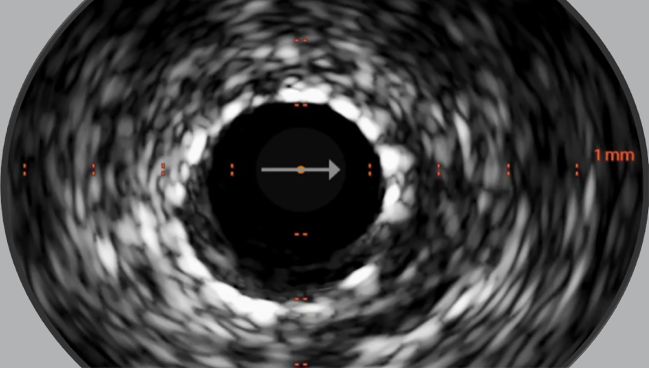

Photo Credit: Adapted from Shlofmitz E. IVUS & OCT image interpretation made easy. Presented at: Cardiovascular Interventions 2024. Torrey Pines, CA.